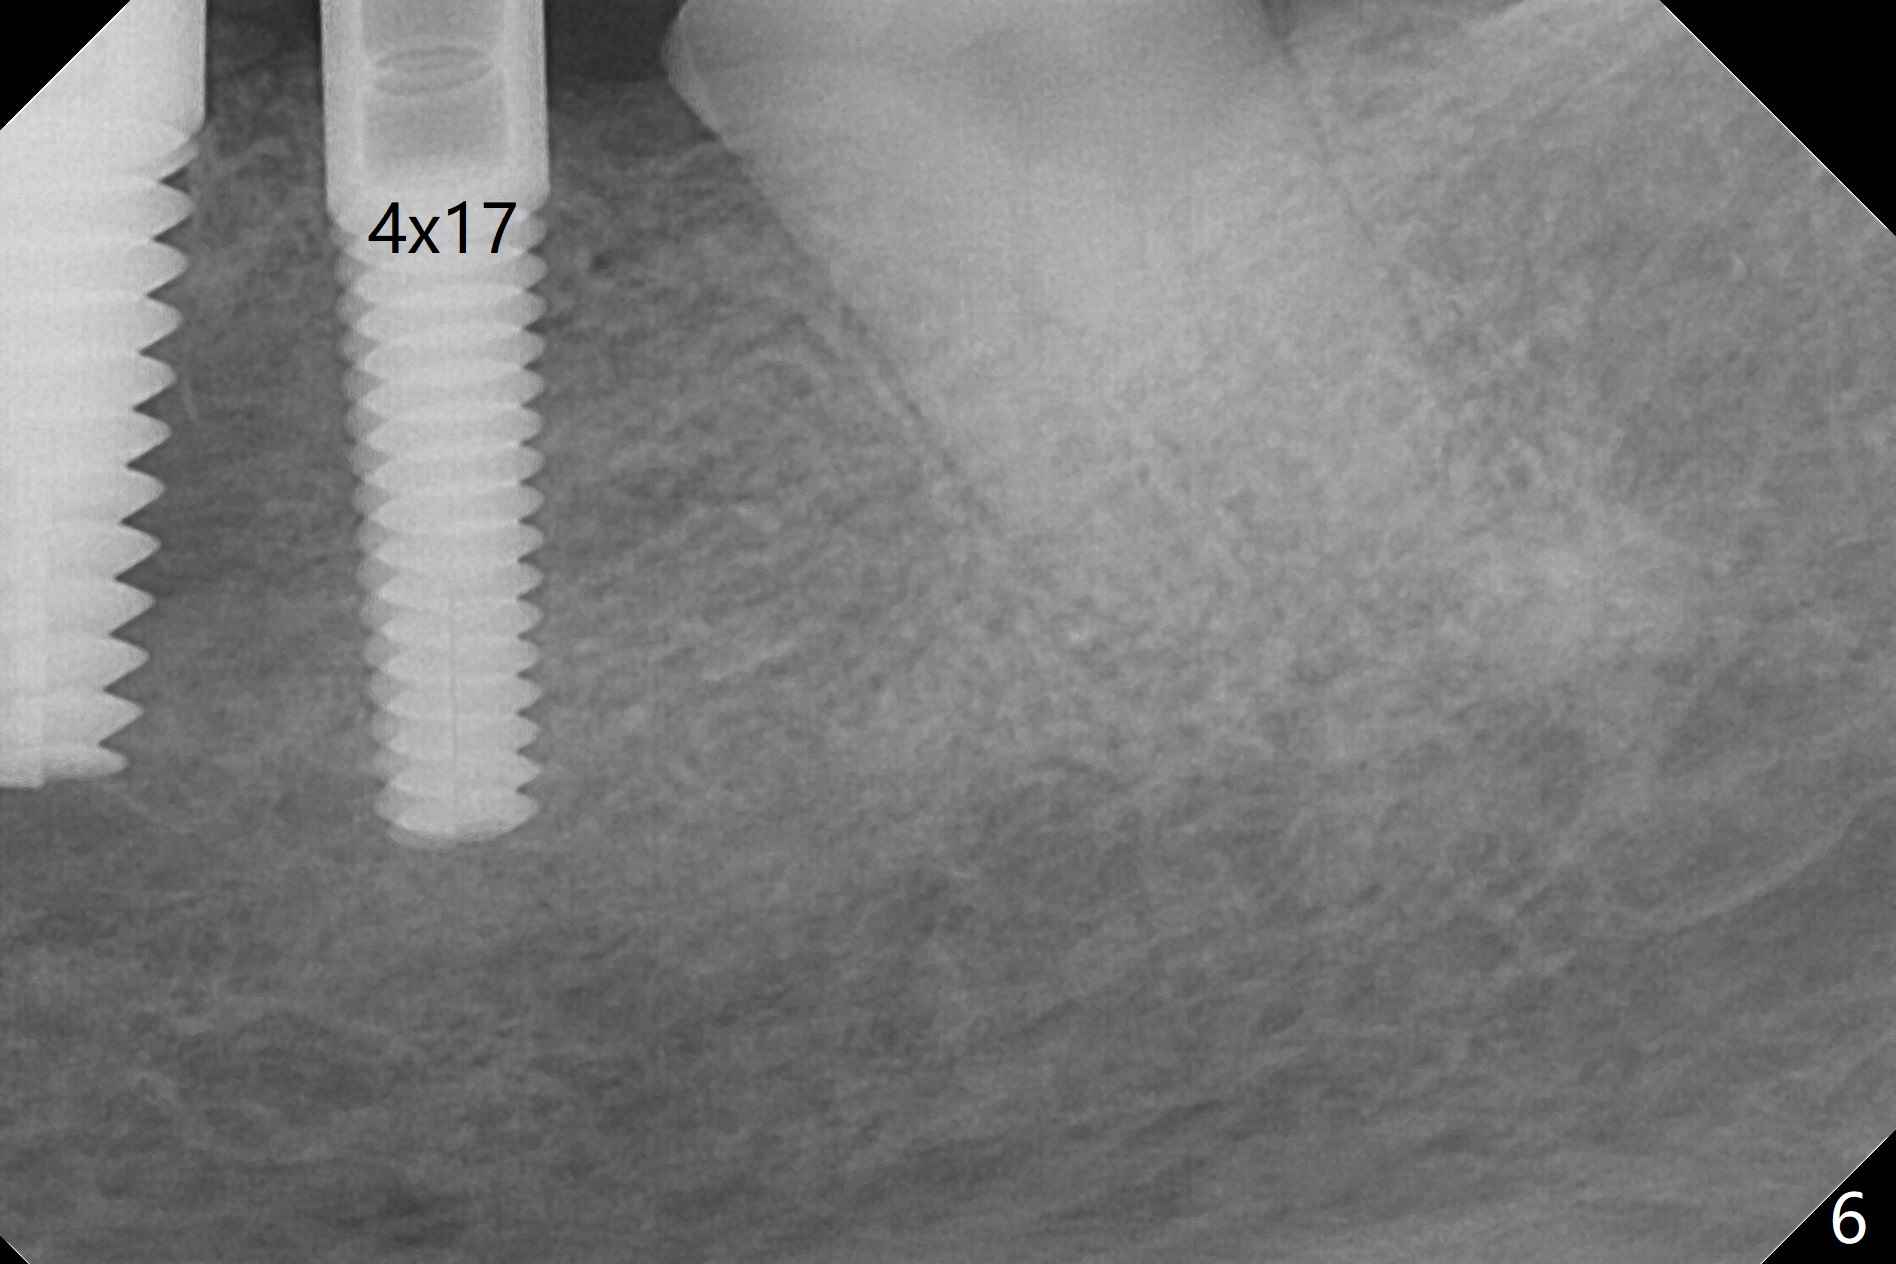

When the tooth #20 is extracted, the buccal and lingual plates are intact, but the apical lesion is deep. A PA is taken (Fig.1). Osteotomy will be established either along the long axis of the original socket (Fig.2 a line) or in the mesial slope (b line). Either osteotomy may damage the Mental Loop (red dashed line). To reduce the complication, osteotomy is being made by inserting 3.8 to 6 mm taps. In fact the 6 mm tap achieves stability (Fig.3,4), but it invades the buccal gap. When the tap is removed, the bottom of the socket is sensitive to probing with oozing from the socket. To reduce further compromise of the buccal space, Lindamann bur is used to remove the bone from the lingual and mesial plate, followed by placing a 6x17 mm implant with >50 Ncm (Fig.5). In fact the implant is placed shallower than the tap. When a 4x17 mm implant is placed at #19, there seems to be clearance from the Inferior Alveolar Canal (Fig.6). Postop there is no paresthesia. The buccal gap is <1 mm, which is filled with Vanilla Graft. After recementing the retainer (crown, C in Fig.7) at #18, periodontal dressing is applied to the sites of #19 and 20. Impression is taken 4 months postop with that of #15.